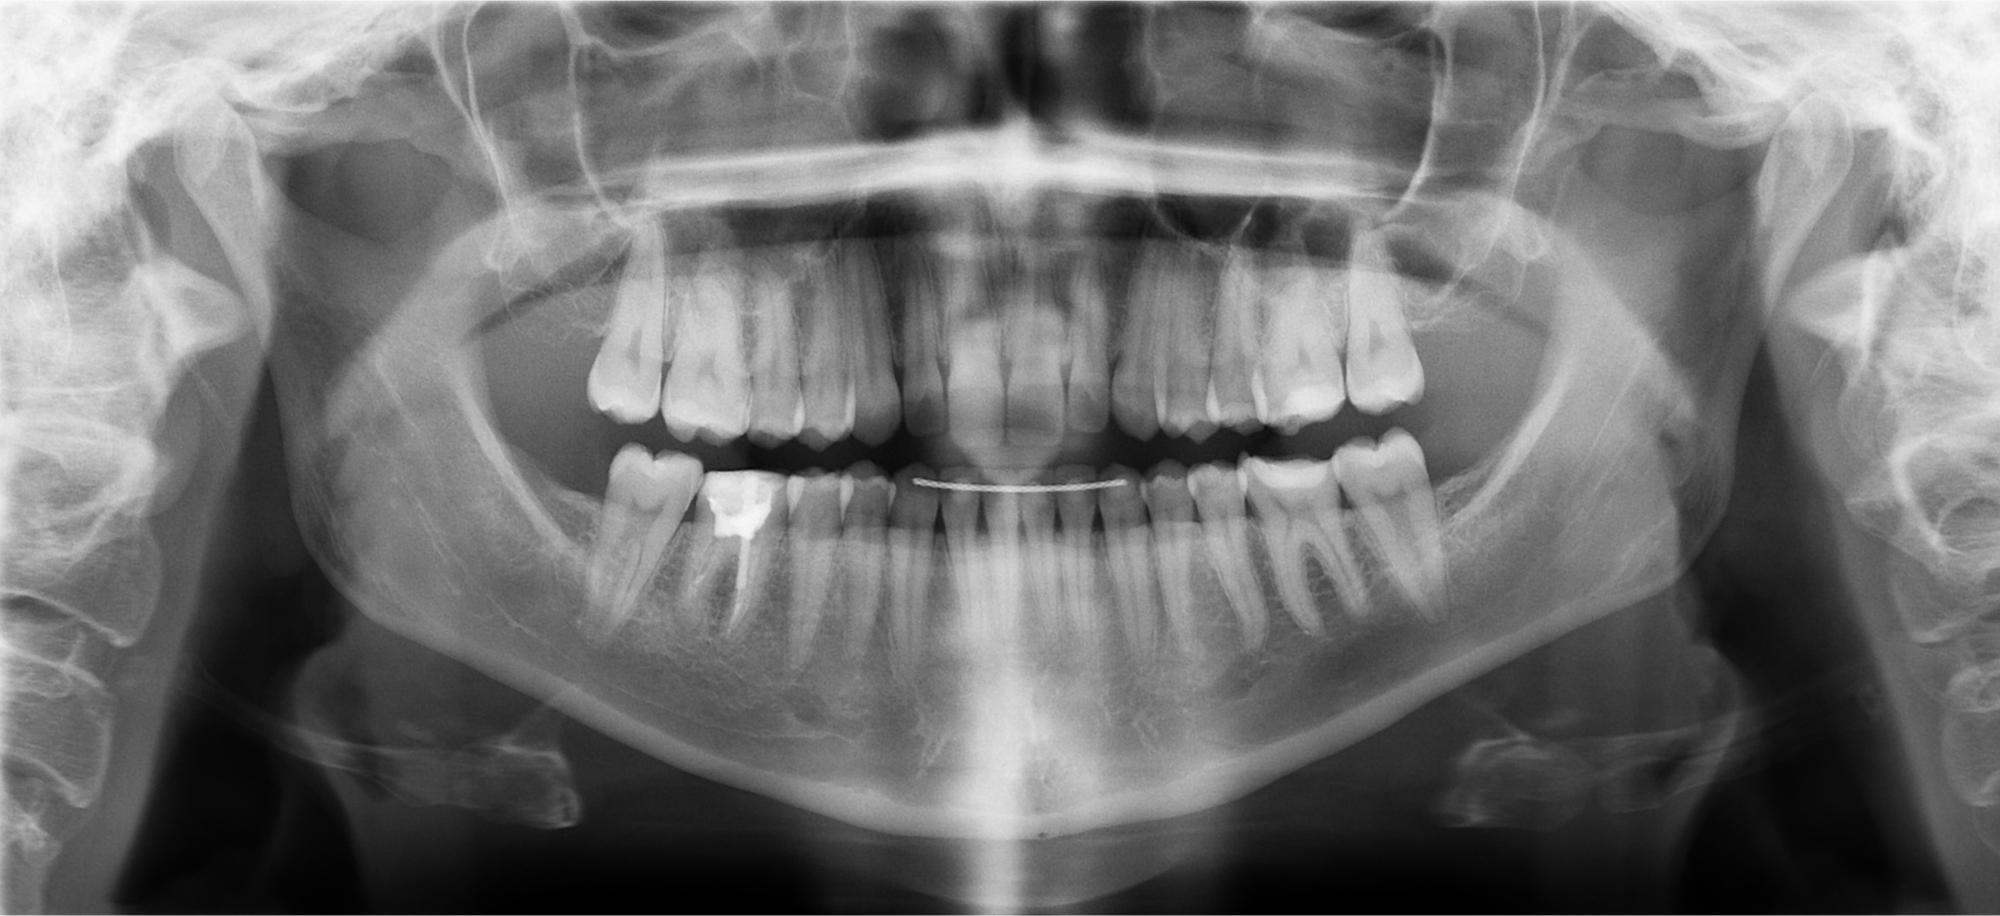

Your evaluation includes a CT scan, comprehensive oral images, sleep assessment, and personalized treatment plan from Dr. Trivedi. If you choose to proceed with the complete solution stack, your evaluation costs will be applied as a discount.

After your evaluation, the doctor reviews your results and explains how your airway structures are impacting your health. You’ll then receive a personalized plan that may include palatal expansion, aligners, or other therapies to optimize your health.